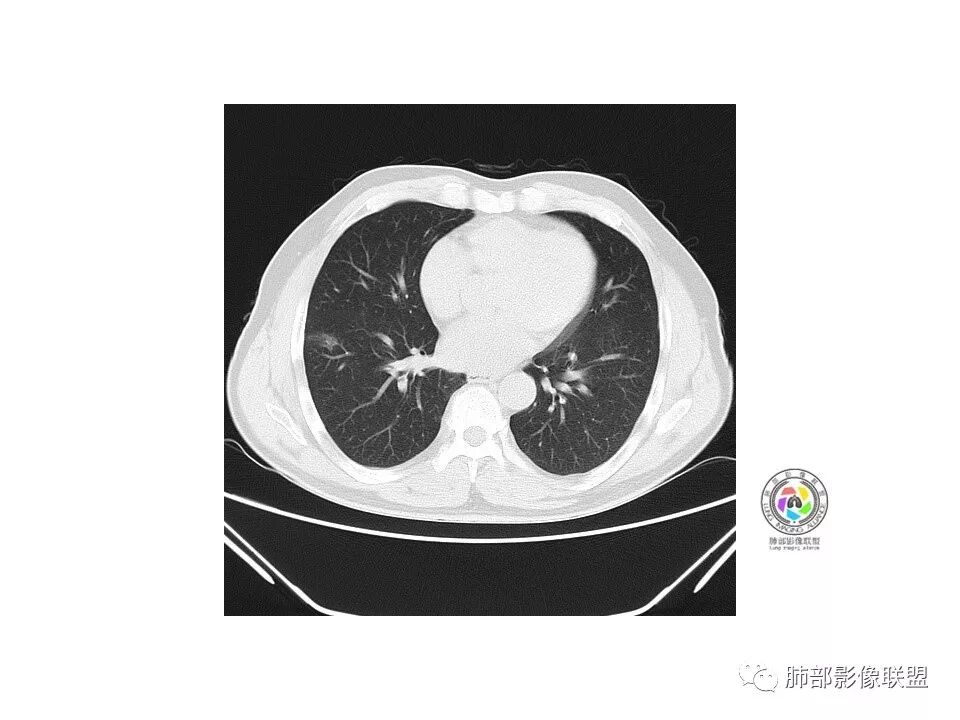

先按临床常规思路抗炎治疗,没有吸收变化后,根据病人意愿可以选择随访观察或者直接手术,腺癌还是得常规考虑

有收缩、有膨隆

右肺下叶前基底段混合磨玻璃密度结节 边缘见月牙铲 部分边缘清 部分似清非清 远端见磨玻璃片影,炎性和粘液腺癌鉴别 先抗炎复查

病史:老年男性,咳、痰三天;

1.纵膈窗未显示;水平裂有轻微凹陷,那个条索影,有形成机理进一步分析;前方那个血管,可能是肺动脉?有一定弯曲度(向病灶),后方这个是肺静脉;3个小叶凹,有可能,受到阻挡,邻近小血管有相应改变;薄层那个细小血管有弯曲,形成部分实性;

2.大小:估计15*10mm左右;

3.CT值:混杂,有些偏高;

4.周围小血管,有形成毛刺趋势;

5.血管:如上述;

6.胸膜和叶间裂:有轻微牵拉;

诊断:浸润性腺癌;鉴别:炎性结节;

处理:炎标、肿标、病史、职业史、抽烟史,既往胸部检查;

流心明智:

老年男性,咳嗽、咳痰3天。胸部CT:右肺下叶前基底段mGGN,边缘清楚,内可见不规则实性成分,病灶可见空泡、毛刺、胸膜牵拉、血管集束征象。考虑MIA可能大,抗炎2W后复查。

老年男性,右下肺前基底段混合GGN,边缘清晰,月牙铲,叶间胸膜牵拉,有轻度收缩力。结合病史抗炎2-3周后复查,消失考虑炎症,变化不大为腺癌。本例总体支持腺癌

老年男性,咳嗽3天,右肺下叶前基底段混合磨玻璃结节,形态不规整,相邻胸膜凹陷,可见血管影,考虑腺癌可能性大,不除外炎症可能,建议抗炎1~2周,1个月复查胸部CT。

右肺下叶mGGN,内部结构紊乱,可见小点状高密度影,边缘清晰,小叶间隔阻挡,轻度收缩力,考虑MIA,常规飞一会20天复查。

右肺下叶磨玻璃影,边界似清非清(考虑部分为血管断面围绕),周边见条索灶,胸膜牵拉弱。我把炎症放前面,建议抗炎治疗后复查除外恶性。

老年男性,右肺下叶前基底段GGN,界清,内部血管结构杂乱,叶间胸膜牵拉。考虑恶性,早期腺癌可能,建议抗炎治疗后复查对比。

右肺下叶前基底段见一磨玻璃结节影,呈分叶状,边缘部分模糊,与胸膜间有长条索粘连,内有增粗的血管影,后者边缘毛糙,考虑微浸润性腺癌,建议抗炎治疗后复查

老年男性,右肺下叶前基底段斜裂旁可见单个混合型磨玻璃结节mGGN,边缘清,内部结构紊乱,进入的血管增粗,支气管关系不好判断,斜裂侧可见牵拉,常规考虑微侵腺癌MIA,建议先抗炎后复查及手术干预。

老年男性,咳嗽咳痰3天。MGGN,边缘见月牙铲、胸膜牵拉,血管移动联通?冠状位隐约可见支气管穿行,考虑MIA,重建冠位可见结节比较靠近叶裂,可积极手术处理。

老年男性,右S8混合磨玻璃结节,边缘尚清晰,局部凹陷,叶间胸膜牵拉,考虑MIA可能大,建议抗炎治疗10天,6-8周后复查